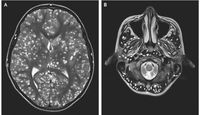

Remaja berusia 18 tahun yang identitasnya tidak disebutkan ini, kehilangan kesadaran setelah mengalami kejang di tubuhnya. Lewat pemeriksaan medis, ditemukan adanya benjolan di permukaan otaknya. Di mana hal ini berakibat fatal untuk keselamatannya.

Dikabarkan Daily Mail UK (28/03), kondisi neurocysticercosis karena ada larva parasit yang ditemukan dalam

daging babi setengah matang. Sehingga ketika parasit ini masuk ke dalam tubuh, mereka menimbulkan efek samping yang menyerang sistem saraf pusat, sehingga memicu kejang.

Menurut catatan medis, remaja ini mengalami kejang tonik-klonik yaitu kejang yang dapat menyebabkan epilepsi. Jika kejang berlangsung lebih dari 3 menit, artinya ada masalah kesehatan yang serius dalam tubuh pasien.

Sehingga ketika diperiksa lebih lanjut melalui tes serum, para dokter memastikan bahwa remaja pria tersebut sudah terinfeksi oleh T. Solium. Atau cacing yang biasa berada di dalam daging babi.